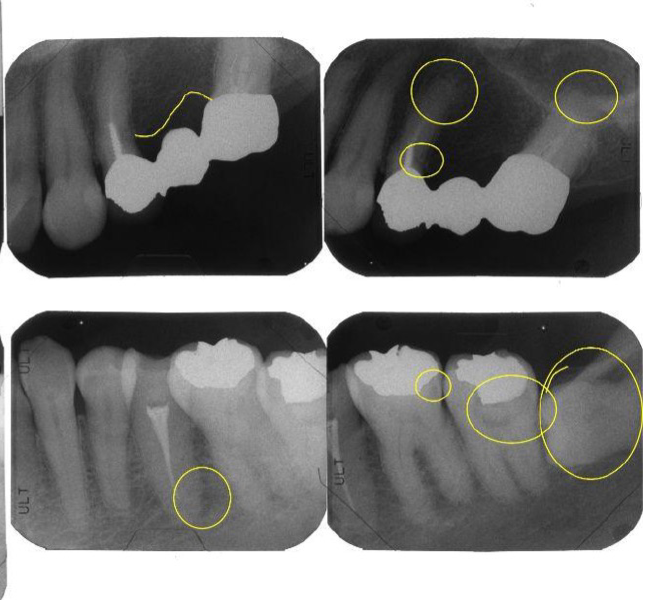

治療前

| 主訴 | 左上のブリッジが欠けた。 金属を白くしたい。歯並びも気になる。 |

| 治療内容 | 全顎治療:歯周病治療、インプラント治療、GBR、根管治療、矯正治療、 ダイレクトボンディング、セラミック治療、親知らずの抜歯 |